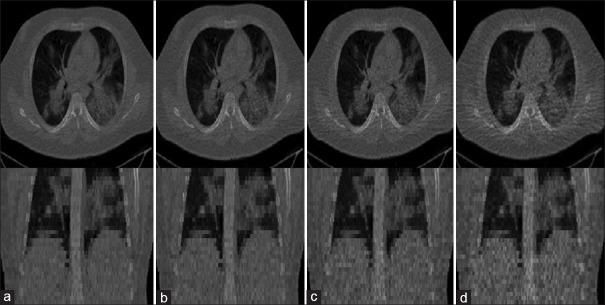

METHODS

In this light, we set out to simulate four reduced dose levels (60% dose, 40% dose, 20% dose, and 10% dose) of standard CT imaging using Beer-Lambert's law across 49 patients infected with COVID-19. Then, three denoising filters, namely Gaussian, bilateral, and median, were applied to the different low-dose CT images, the quality of which was assessed prior to and after the application of the various filters via calculation of peak signal-to-noise ratio, root mean square error (RMSE), structural similarity index measure, and relative CT-value bias, separately for the lung tissue and whole body.

RESULTS

The quantitative evaluation indicated that 10%-dose CT images have inferior quality (with RMSE = 322.1 ± 104.0 HU and bias = 11.44% ± 4.49% in the lung) even after the application of the denoising filters. The bilateral filter exhibited superior performance to suppress the noise and recover the underlying signals in low-dose CT images compared to the other denoising techniques. The bilateral filter led to RMSE and bias of 100.21 ± 16.47 HU and - 0.21% ± 1.20%, respectively, in the lung regions for 20%-dose CT images compared to the Gaussian filter with RMSE = 103.46 ± 15.70 HU and bias = 1.02% ± 1.68% and median filter with RMSE = 129.60 ± 18.09 HU and bias = -6.15% ± 2.24%.

CONCLUSIONS

The 20%-dose CT imaging followed by the bilateral filtering introduced a reasonable compromise between image quality and patient dose reduction.